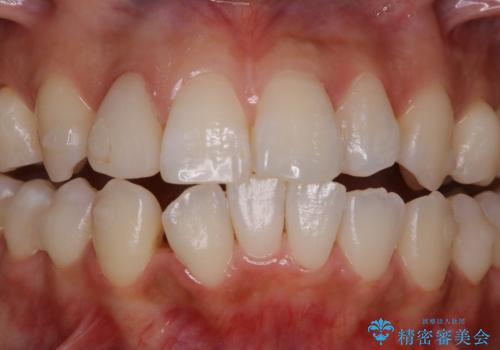

- インビザラインでのマウスピース矯正中の方です。歯についてしまったステインが気になり綺麗にしたいとのことでした。PMTC60分コースを行いました。

PMTC(保険外治療)は、毎日の歯磨きで落としきれない汚れや、コーヒ、紅茶・タバコのヤニなどの着色も除去します。目には見えない歯と歯の間・歯肉の境目・インビザライン中はアタッチメント周囲などに残っているプラーク(歯垢)もしっかり取り除きます。PMTCでは専門的な機械や材料を使用して、徹底的に汚れを除去するため、虫歯・歯周病・口臭予防などにつながります。

またPMTCを行うことで、ご自身本来の歯の色になり自然な明るさになります。

口元が自然な明るさになることで、より清潔感のある印象になるため結婚式・行事やイベント前などにもPMTCを行うはおすすめです。